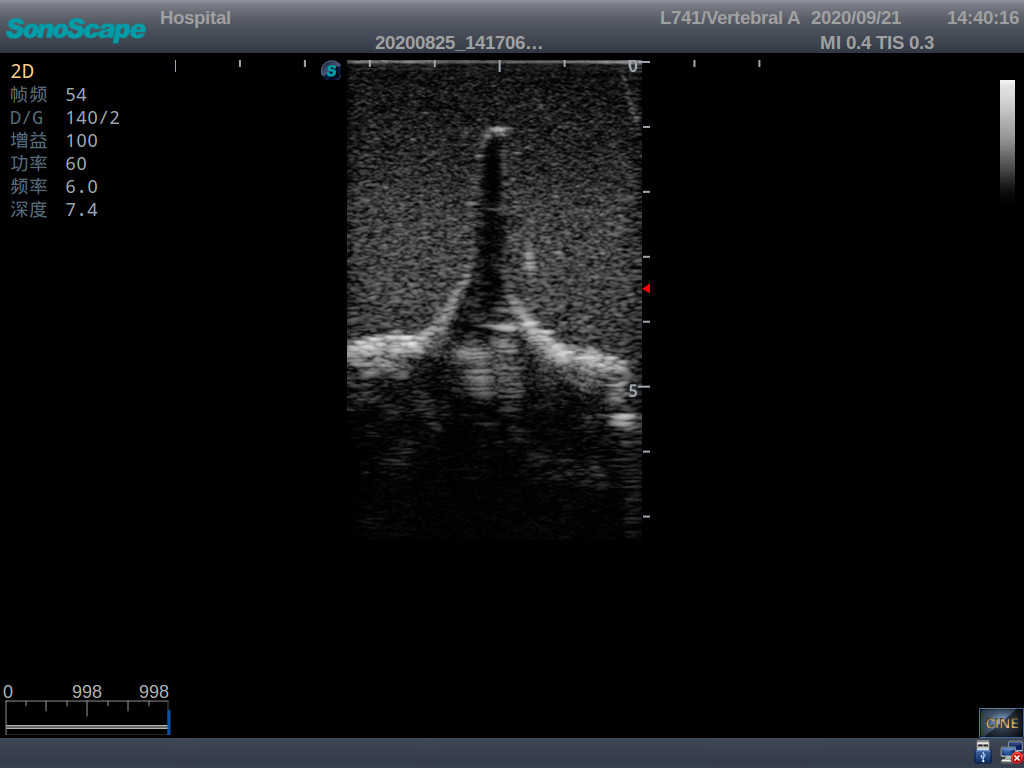

2) Real clinical ultrasound images

3) Compatible with various real ultrasound machines